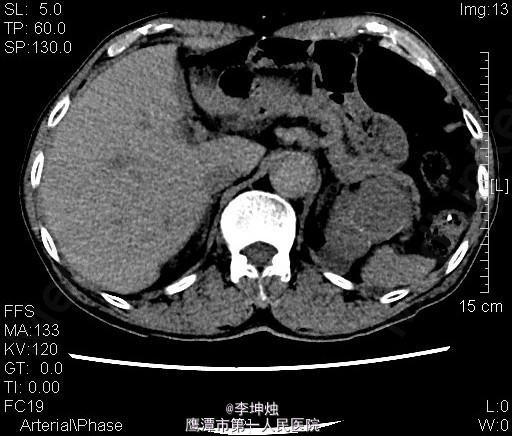

3、查体:增加腹压或站立位时右侧腹股沟隆起,可触及一大小约4*5cm肿物,可进入同侧阴囊,质软,边界清,无压痛,压迫肿物表面后嘱患者咳嗽,有冲击感,平卧或用手可将肿物回纳腹腔。直肠指检:肛门括约肌稍松弛,前列腺明显增大,大小约:3×4cm,表面光滑,质韧,边缘清楚,中央沟变浅,未触及明显结节,指套未见染血。 4、辅助检查:当地人民医院,腹部CT提示考虑左肾Ca可能;慢性膀胱炎;右侧腹股沟区见肠管嵌如;前列腺增生。我院双肾CT平扫+增强:左肾上极肿块,考虑肾癌,侵犯左肾上部皮髓质及左肾上盏,可疑侵及胰尾部。

5、诊断:左肾占位,左肾ca? 6、处理:入院完善相关检查,核素肾动态显像:双肾灌注轻度降低、功能中度受损。双肾+肾上腺CT:左肾上极肿块,考虑肾癌,侵犯左肾上部皮髓质及左肾上盏,可疑侵及胰尾部。排除手术禁忌后,行“腹腔镜下左肾根治+肾门淋巴结清扫术”,术后予“头孢哌酮钠舒巴坦钠(舒普深)”抗感染、抑酸、营养补液等处理,术后恢复可。病理提示嗜酸性细胞瘤。